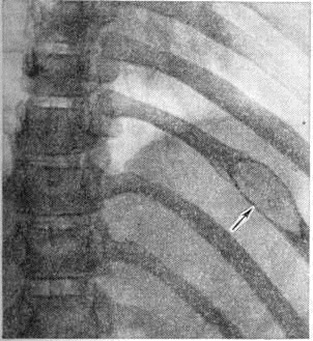

Рис. 12.

Рентгенограмма (фрагмент) грудной клетки ребёнка 8 лет при миеломной болезни; прямая проекция: вздутие X ребра с дефектом костной ткани (указано стрелкой).